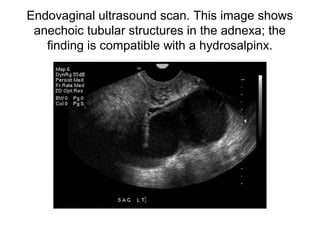

Endovaginal ultrasound scan. This image shows

anechoic tubular structures in the adnexa; the

finding is compatible with a hydrosalpinx.